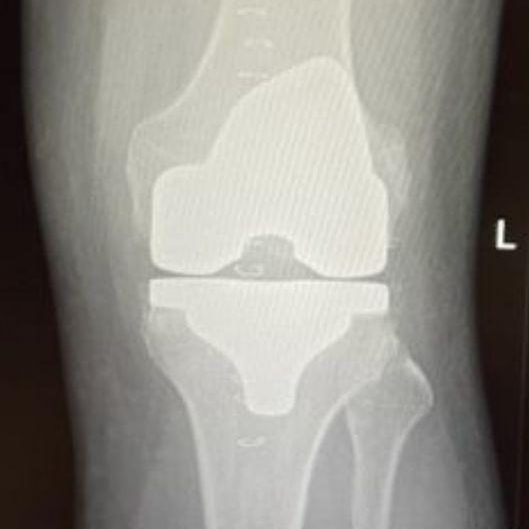

Knee Replacement Surgery

Dr. Terreblanche’s expertise in a full knee replacement surgery ensures that you receive the highest level of care. We guide you through the entire process, from pre-surgical planning to post-operative rehabilitation, to achieve the best possible results.